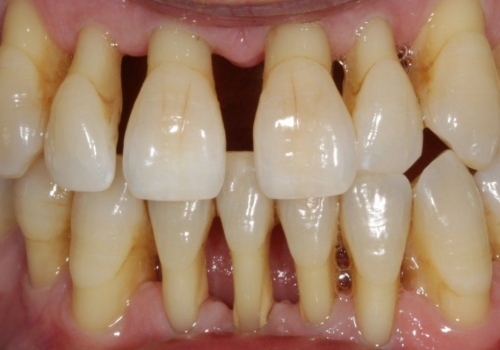

Parodontit tədricən dişətrafı sümük toxumasının itirilməsinə və bakterial plakın daha dərin təbəqələrə keçməsi ilə birlikdə ciddi dərinliklərə çatan sümük defektlərinin (və ya ciblərinin) yaranmasına gətirib çıxarır. Sümük toxumasının itkisi müəyyən bir zaman sonra dişlərdə ciddi hərəkətliliyin yaranmasına və qısa bir müddət sonra itirilməsinə gətirib çıxara bilir.

- Dişlərin laxlaması

- Diş ətlərində çəkilmə